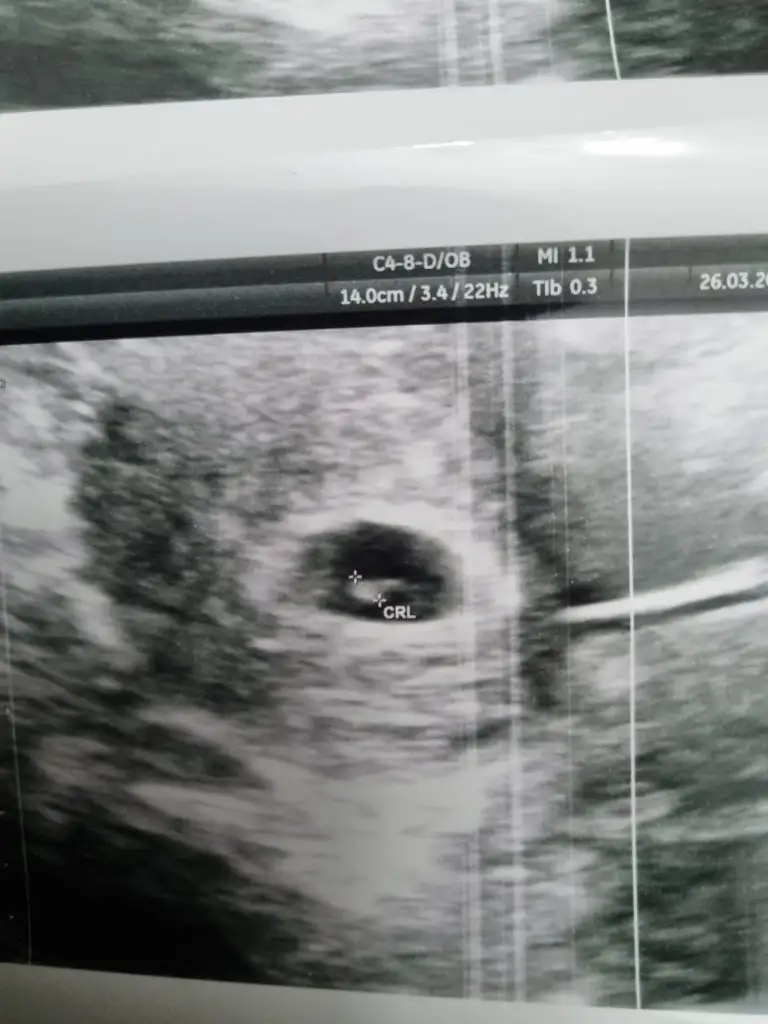

Erkek cnm nubu dikMerhaba kızlar üstte gördünüz resmî yorumlayabilirmisiniz çok merak ediyorum cinsiyetini

Bebeğin yonu ne tarafa bakıyor eger assagi dogru ise erkek derim ama yukari dogru bakıo sa kiz. Anlayamadım durusunu kafasina gore yukarı bakıyor sankiAllah rizasi icin 12 +4 yorum yapabilirmisiniz

Kız gibi duruyor bence kız olcakKizlar bana da bakar msnzzz